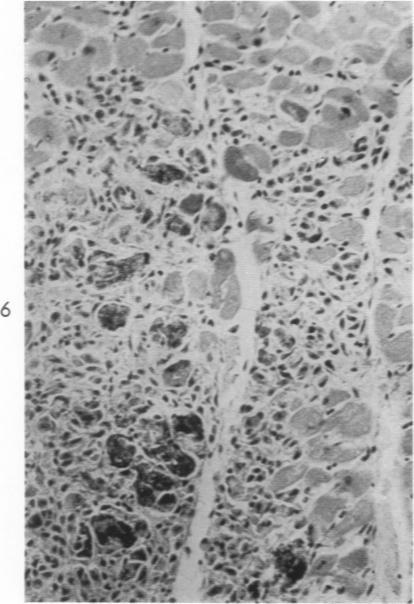

Homotransplantation of the Canine Liver as an Orthotopic Vascularized Graft: Histologic and Functional Correlations During Residence in the New Host.

Am J Pathol. 1962 Nov;41(5):501-19.